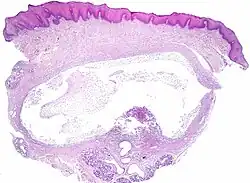

Die Ranula (lateinisch für „Fröschlein“) – auch Froschgeschwulst oder Mundbodenzyste – ist eine unterhalb der Zunge gelegene, mit eingedicktem Speichel gefüllte Retentionszyste. Ursprung der Speichelretentionszyste ist in der Regel der Ausführungsgang der Unterzungenspeicheldrüse (Glandula sublingualis major).

Typischerweise findet sich eine sicht- und tastbare verschiebliche prall-elastische Schwellung unter der Zunge am Mundboden. Zur Abgrenzung gegenüber anderen Raumforderungen dienen die Eigenschaften, dass eine Ranula eine dünne Wand hat und Speichel enthält. Sie entspricht also einer Mukozele.